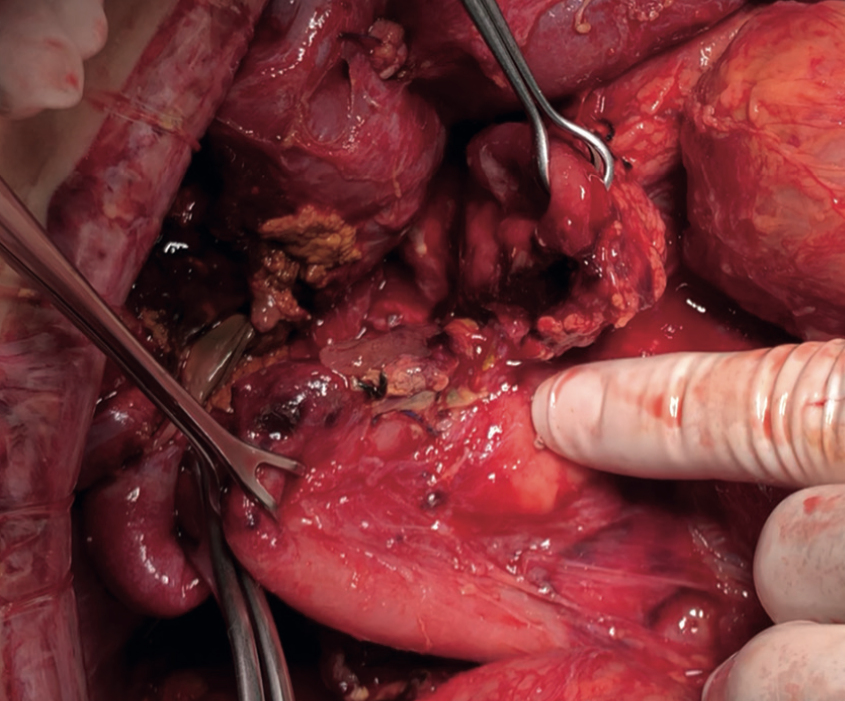

Gabriela Susana Ochoa Suazo, Nicolas Jarufe Cassis, Martin Dib Marambio

|

|

|